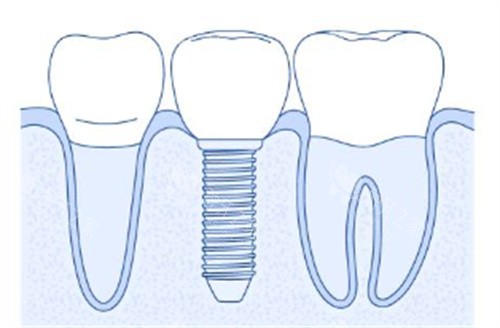

种植牙材料展示

种植牙连桥冠示意图